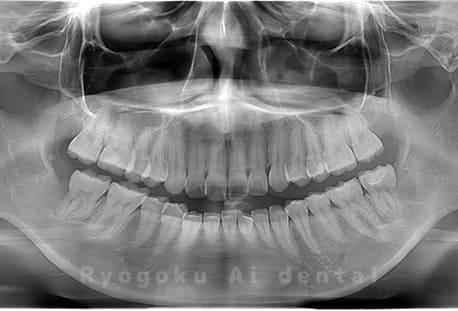

真っ直ぐ生えている親知らず

親知らずが真っ直ぐ生えているタイプです。

このタイプは真っ直ぐ生えていて咬み合わせに問題がなければ、抜歯しないケースもあります。ただし、虫歯になっていたり、痛みがあったり、咬み合わせが悪かったりすると抜歯をおすすめします。